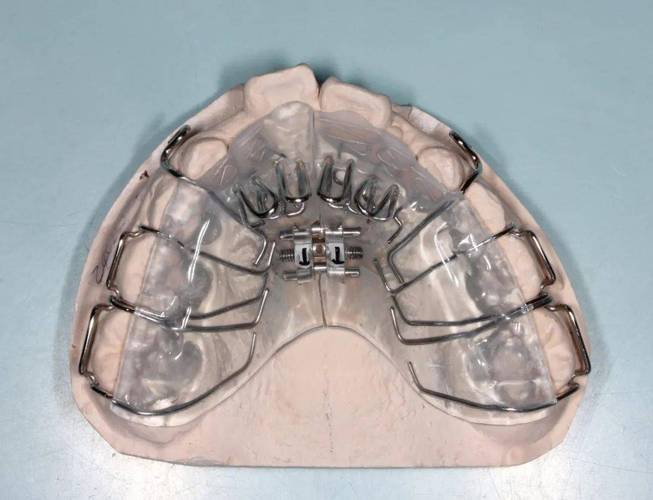

正畸方形勾托槽是口腔正畸治疗中常用的固定矫治器核心组件,其设计融合了力学原理与临床需求,通过精准传递矫治力引导牙齿向理想位置移动,与传统圆形托槽相比,方形勾托槽的核心特征在于“方形槽沟”与“勾状结构”的协同作用:基底多为金属(如不锈钢)或陶瓷材质,经酸蚀处理以增强与牙面的粘接固位力;槽沟呈标准方形,内径与方形弓丝(如镍钛方丝、不锈钢方丝)精准匹配,形成“面面接触”的嵌合关系;翼部设有结扎翼,便于医生用结扎丝或弹性圈固定弓丝;槽沟两侧或底部则设计有“勾”,辅助防止弓丝滑脱,增强稳定性,这种结构使其在复杂牙齿移动中展现出独特优势。

方形勾托槽的核心优势在于高精度的三维控制能力,方形槽沟通过限制弓丝在槽沟内的旋转和倾斜,使矫治力能够精准作用于牙齿的近远中、垂直向及颊舌向三个维度,在矫正牙齿扭转时,方形弓丝嵌入槽沟后,可通过“旋转加力”直接调整牙冠方向;在压低前牙或伸长后牙时,槽沟的方形结构能避免弓丝发生“颊舌向摆动”,确保力量垂直传递,部分方形勾托槽搭配低摩擦材料(如陶瓷滑道)或自锁设计,可减少弓丝与托槽间的摩擦力,降低牙齿移动阻力,缩短治疗周期,尤其适用于中重度拥挤、深覆合、深覆盖等复杂病例。

在临床应用中,方形勾托槽的适用范围广泛,青少年恒牙列早期矫治中,可用于解决牙列拥挤(通过扩弓或邻面去解除拥挤)、牙齿异位萌出等问题;成人正畸中,则能满足对牙齿转矩、轴倾度的精细调整需求,如改善“露龈笑”时需压低上前牙、纠正骨性畸形导致的牙齿代偿等,对于追求美观的患者,还可选择陶瓷材质方形托槽,其颜色接近牙齿,减少“钢牙” appearance,提升治疗依从性。